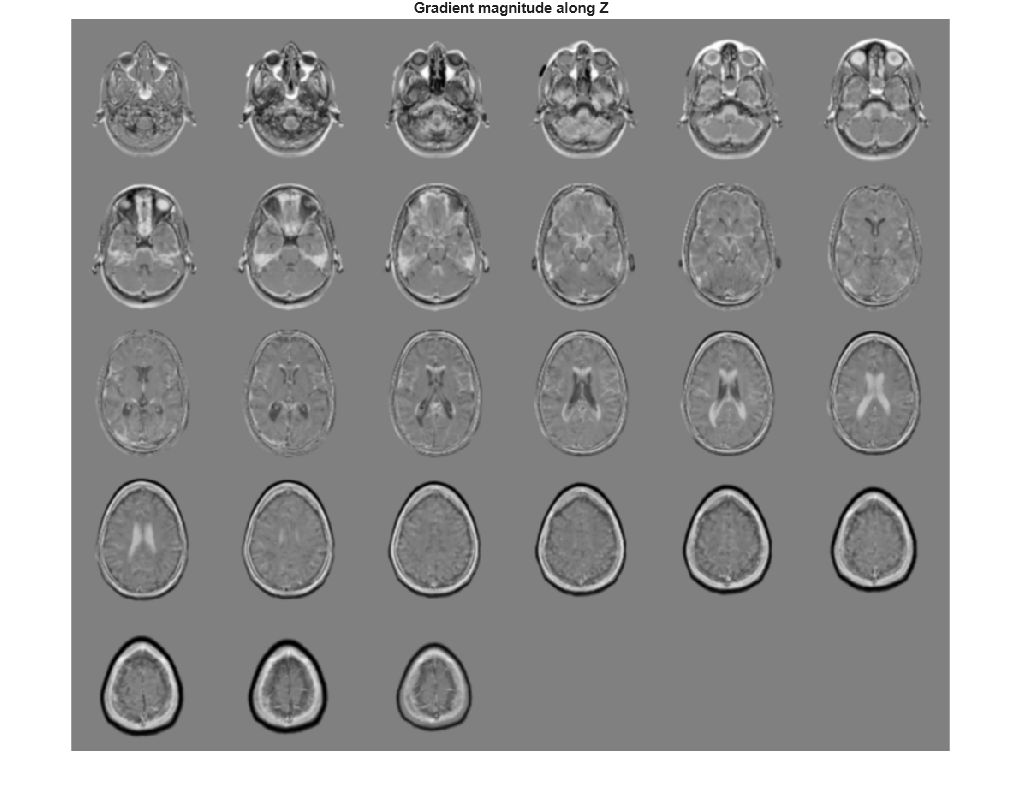

Visualize the directional gradients as a montage.

figure, montage(reshape(Gz,sz(1),sz(2),1,sz(3)),'DisplayRange',[]) title('Gradient magnitude along Z')